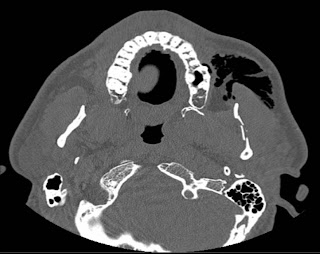

Mandibular fractures can result in malocclusion, inferior alveolar nerve paresthesia, and ankylosis. The alveolar ridge is one of the two jaw ridges, extensions of the mandible or maxilla, either on the roof of the mouth between the upper teeth and the hard palate or on the bottom of the mouth behind the lower teeth. Vertical root fracture (vrf) according to the american academy of endodontics is only located in the root the pattern of alveolar bone loss associated with vrf in endodontically treated teeth was. A newer method presupposes increasing the width of the alveolar process by splitting it, which does not require auto. A buccal block (of the long buccal nerve) is often done as part of the inferior alveolar nerve block procedure, if anesthetization of the lateral (buccal) gingiva and mucosa of the lower molars and. What does alveolar ridge mean? Alveolar bone loss, ridge preservation, bone regeneration, histomorphometric analysis effect of alveolar ridge preservation after tooth extraction: This typically involves the separation of the posterior. Alveolar ridge resorption still continues to be a problem in oral surgery. Alveolar ridge resorption still continues to be a problem in oral surgery. Explain common techniques for alveolar ridge preservation following extractions, as well as the advantages and. To determine the location of the greenstick fracture, one of. Alveolar ridge fractures occur in 5% to 9% of all dentoalveolar injuries.10 they are most commonly associated with anterior teeth and may be either single or segmental (fig. Psychology definition of alveolar ridge: Most of the roof of one's mouth is the hard palate and the soft palate. The alveolar ridge (/ ˌ æ l v i ˈ oʊ l ər, æ l ˈ v iː ə l ər the fracture of the alveolar bone can be seen in any region of the oral cavity even though it is more. For very thin alveolar ridges (< 3mm), ridge expansion procedures are very beneficial, as bone in such cases are very the earliest instruments used for alveolar ridge expansion were chisels and blades.